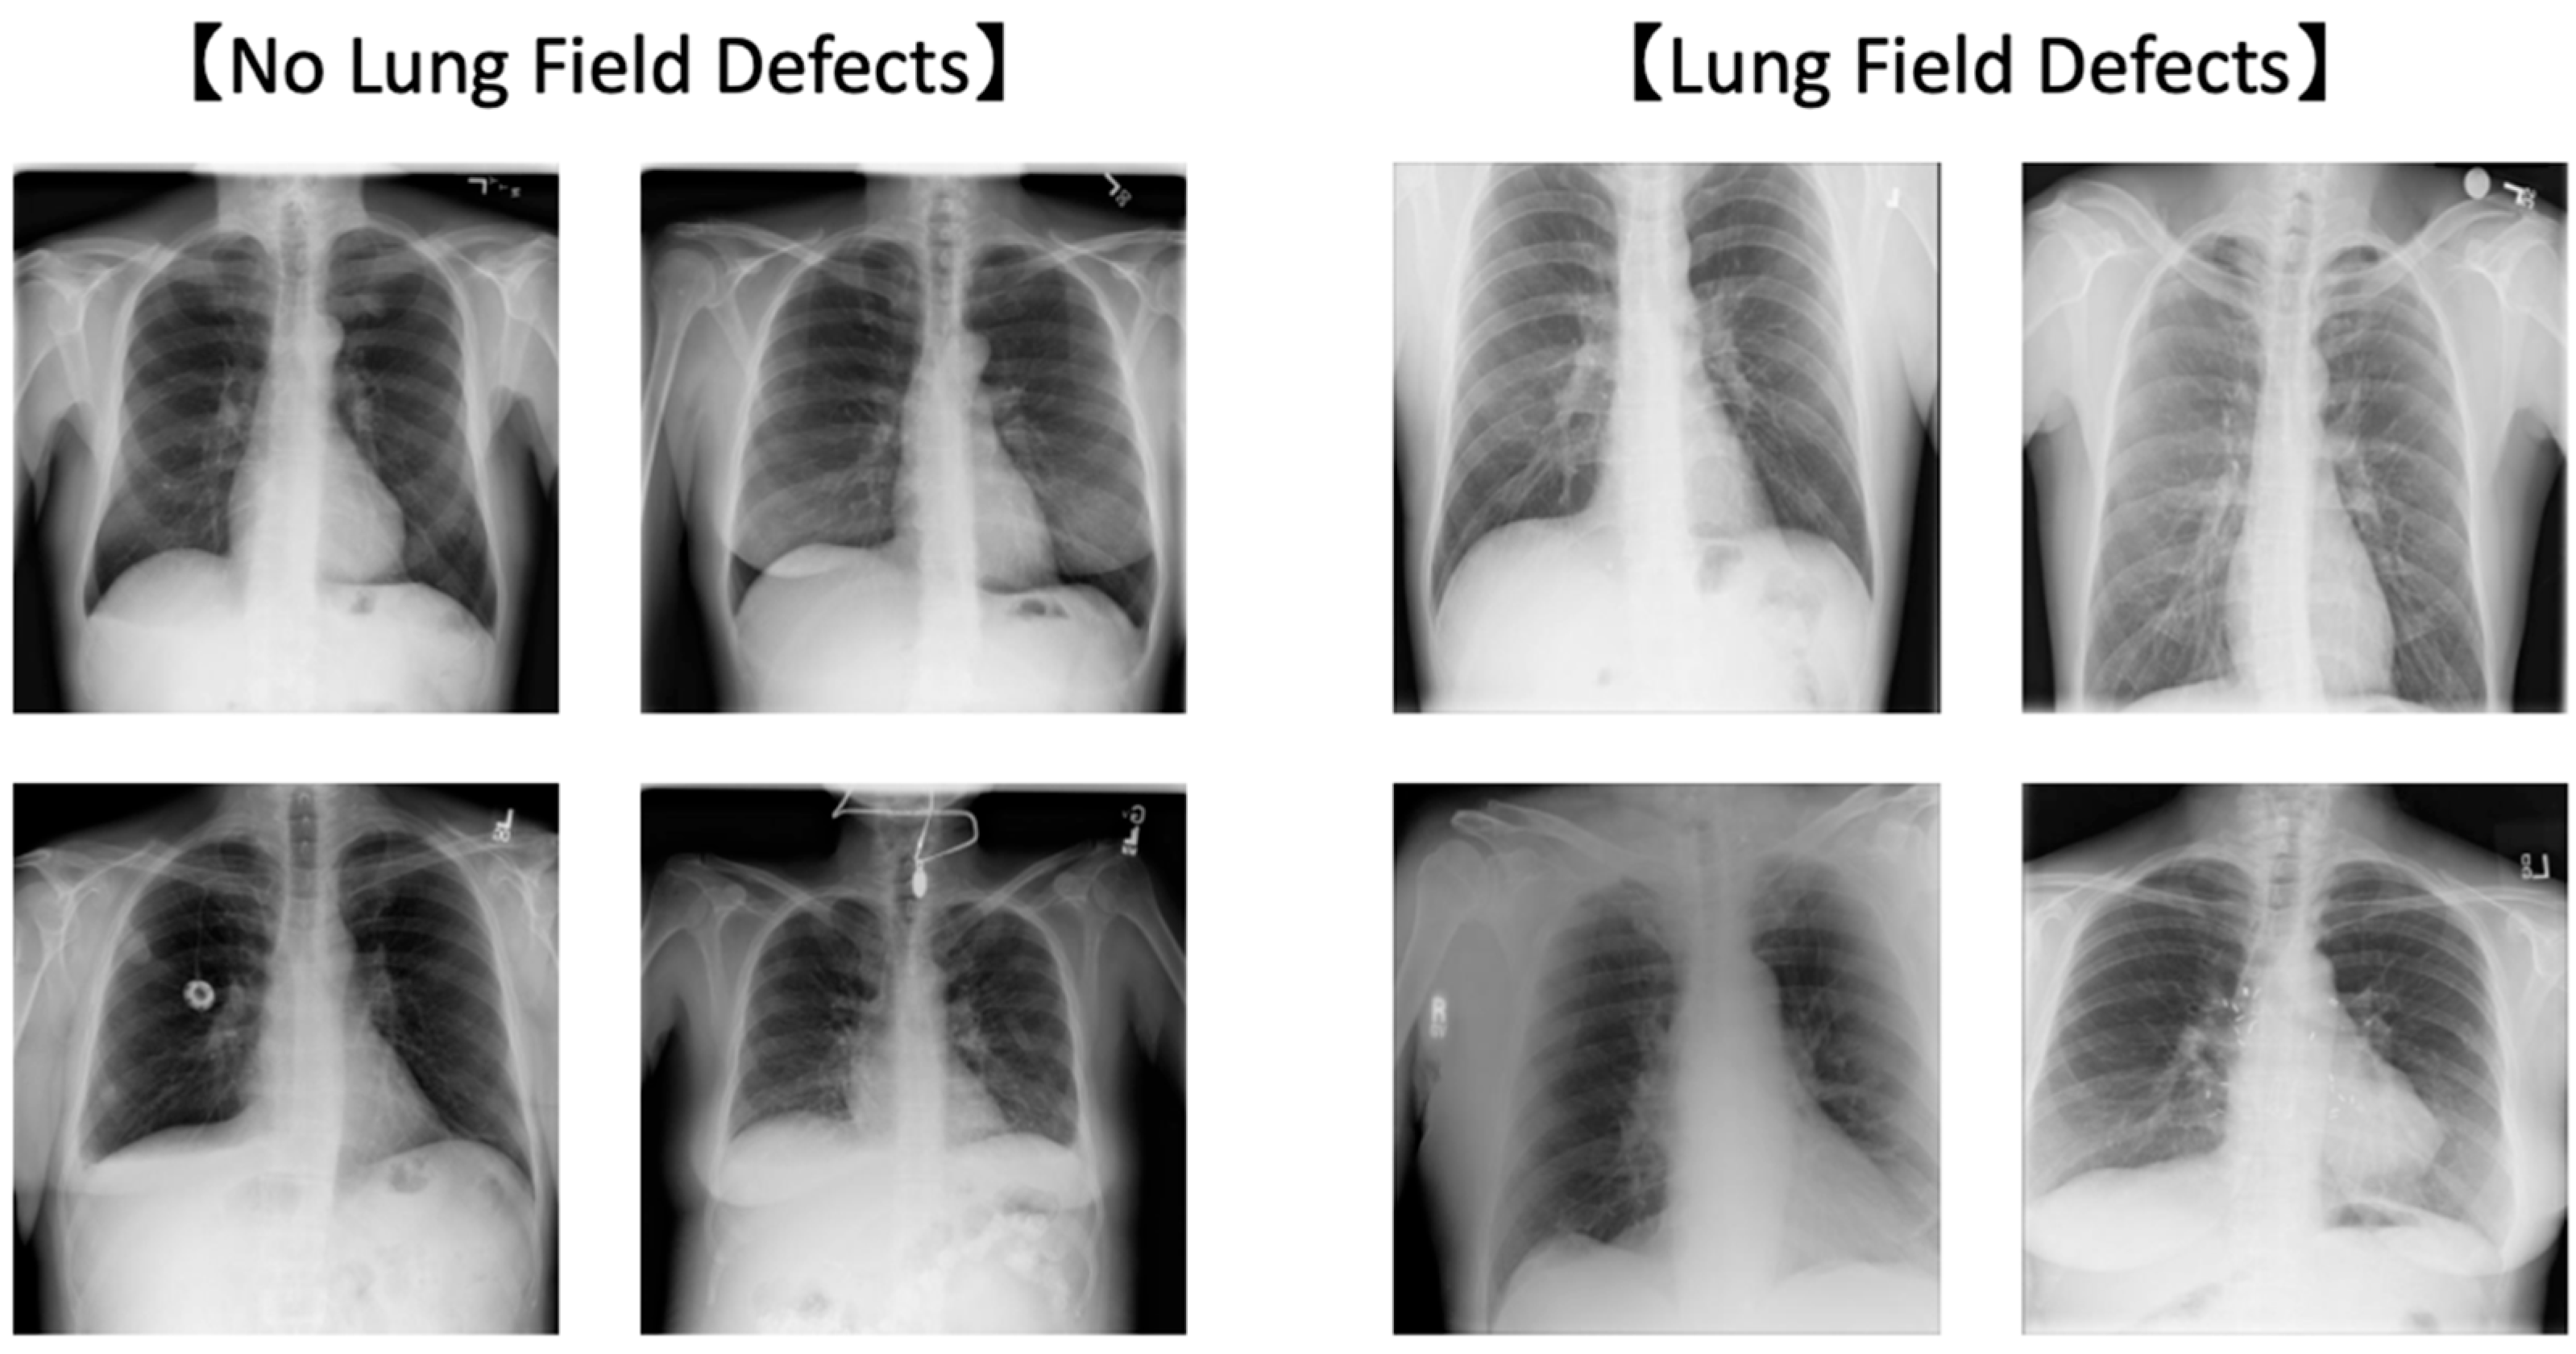

We used 1000 of 4809 images in which the lung field area was depicted without defects (defined as “OK”) and 1000 images in which the lung field area was depicted with defects (defined as “NG”) (Figure 1) and created a CLM for the lung field defects.

Figure 1. Representative examples with and without lung field defect.